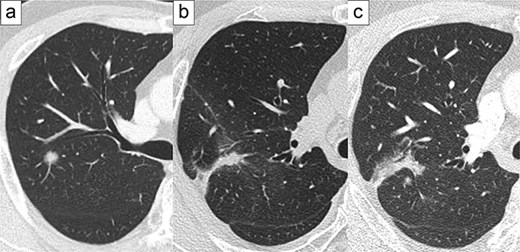

Microscopically, papillary adenocarcinoma, fibrosis, foreign body-type giant cells, and cholesterol clefts (Fig. 2) were observed. Therefore, the lesion was diagnosed as a local recurrence of adenocarcinoma post-cryoablation.

(a) Papillary adenocarcinoma, fibrosis, as well as foreign body-type giant cells and cholesterol clefts (hematoxylin and eosin staining, 2× magnification). (b) Papillary adenocarcinoma was dominantly observed (hematoxylin and eosin staining, 20× magnification). (c) Foreign body-type giant cells and cholesterol clefts were observed along with fibrosis (hematoxylin and eosin staining, 5× magnification).